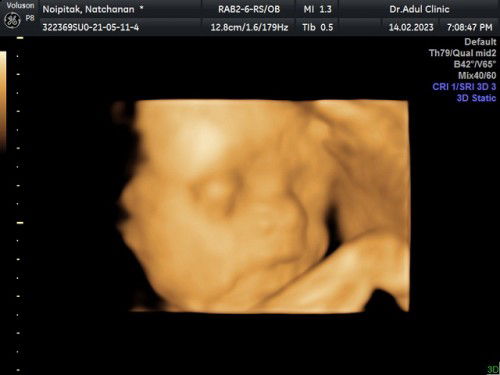

แชร์ความน่ารัก 4D 27w6d 💖👶🏻

มาแชร์รูปเจ้าตัวน้อย 24วีค ค่ะ 💖